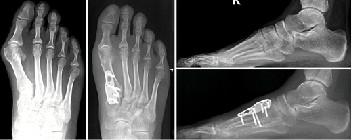

如果非手术治疗失败,可以考虑手术治疗。(证据级别:4)在选择手术前,必须确定拇外翻的严重程度。为了做到这一点,使用了负重平片射线照相术。

根据损伤的严重程度,我们可以采用以下几种外科手术:

Scarf Procedure

当畸形中等至严重时,Scarf Procedure是常用的选择。从内向外沿跖骨干纵轴截骨。将跖骨头截骨块移向外侧,并用两个螺钉固定。

Lapidus关节融合术

当观察到严重的畸形时,这是另一种选择。通过切除内侧楔形关节软骨和第一跖骨基部,两者融合。用钢板或螺钉固定。

术后管理